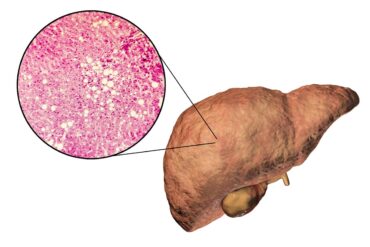

Quanto tempo demora para reduzir a gordura no fígado com bons hábitos

Conhecida como gordura no fígado, a esteatose hepática é uma condição que ocorre quando há um acúmulo grande de gordura nas células do órgão. A...